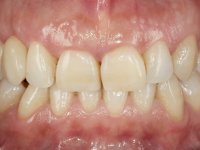

Female patient, 43 years old, non-smoker. Showed an edentulous space in the upper right canine area, resulting from tooth 1.3 impaction. The space had a mesio-distal diameter reduced to the normal size of the upper canine. This is consistent with the presence in the arch of the deciduous canine up to two years ago). Orthopantomography allows clearly view of tooth 1.3 impaction.The patient has a thick gingival phenotype and tolerable oral hygiene.

To define the dental zone to be covered by the Maryland bridge retainers, the patient was asked to perform maximum intercuspidation movements, and the contact points were marked with articular paper. Tooth preparation of the interproximal surfaces was made, to create a prosthetic insertion axis. It was sought that the mesio-distal diameter at the incisal level was equal to the diameter mesio-distal at the cervical level, that is to say, the interproximal walls were parallelized. Tooth preparation was done with fine grain diamond drills, and later polishing was done with abrasive discs. Color information was collected even before confection of the impression, to avoid dehydration of the arcade. Definitive impression was made using wash technique impression with silicone of heavy and regular consistency, both with fast setting, and a working plaster model was prepared in the lab. A laboratory scanner was used to scan the working model, and later, the infrastructure for the Maryland bridge was made using a CAD-CAM process. Ceramic was placed on this subframe. A ceramic adhesive was applied to the internal surface of the wings and connectors, which would enable bonding to the adjacent teeth. The adhesive bridge was bonded in the mouth following the conventional bonding technique. After bonding, the protrusion and laterality movements were carefully checked to avoid undesirable contacts.